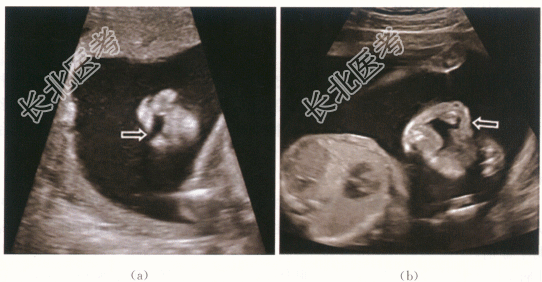

1.病史

患者,女性,23岁,孕24周2天,行常规产前检查。自诉一年半前因TSH4.18mIU/L在内分泌科会诊后予左甲状腺素(优甲乐)0.5粒qd口服,孕期随访,调整用药,现仍为0.5粒qd口服。既往2年前因“胎儿唇腭裂”引产一次。否认家族遗传病史。未行唐氏筛查检查。

二、影像资料

- 简答题1、患者的诊断及超声依据是什么?